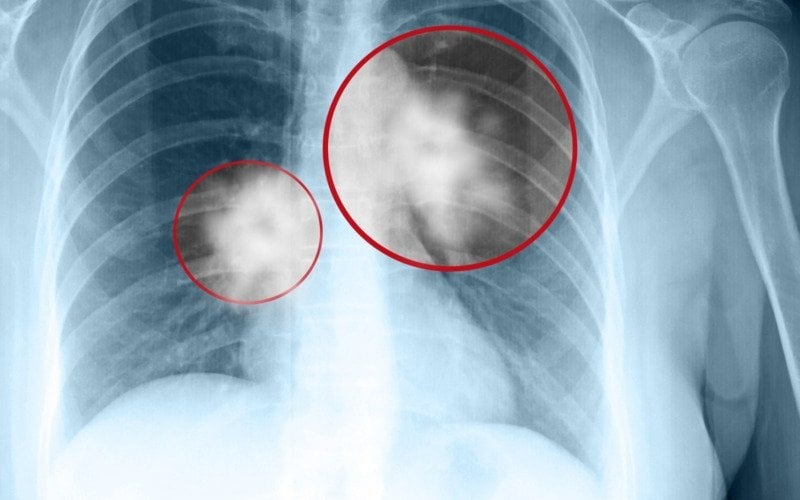

Các u nấm Aspergillus thường xuất hiện trong các hốc lao phổi sau khi điều trị. Do đó, chúng thường được phát hiện nhiều nhất ở các vùng phân thùy trên và dưới của phổi. Trên X-quang ngực, thường thấy một khối u tròn hoặc hình trứng trong một hốc (có đường kính khoảng 3-5 cm). Vùng không khí xung quanh u nấm có hình dạng như lưỡi liềm, được gọi là dấu hiệu Monod. Vị trí của u nấm có thể thay đổi tùy thuộc vào tư thế khi chụp X-quang.

Trên hình ảnh cắt lớp CT scan, u nấm phổi Aspergillus thường chỉ là một khối u tròn trong một hốc. Dấu hiệu Monod về không khí xung quanh u nấm thường hiển thị và sự di động của khối u có thể được chứng minh khi bệnh nhân thay đổi giữa tư thế nằm sấp và nằm ngửa. Đôi khi, u nấm có thể lấp đầy toàn bộ hốc, làm mất dấu hiệu về không khí xung quanh và không còn di động được nữa. Do tình trạng viêm và hình thành mô xung quanh mạch máu, động mạch phế quản xung quanh có thể phì đại và màng phổi lân cận cũng có thể bị đặc hóa.